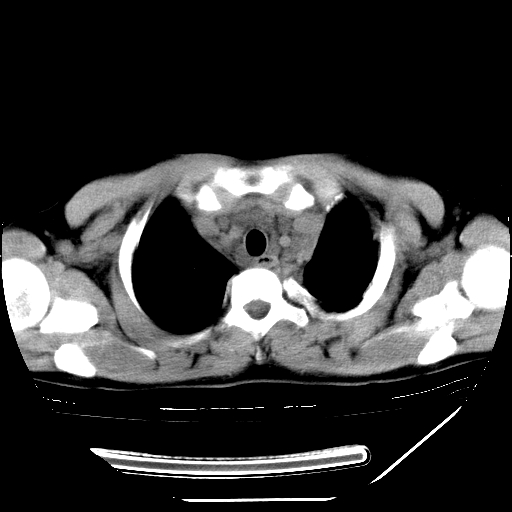

男,13岁,咳嗽、咳痰伴发热一周。

上纵隔课件多枚淋巴结,部分相互融合,左侧支气管壁增厚,肺纹理较右侧增粗,患者,男,13岁,

中上纵隔见多枚淋巴结肿大,部分相互融合成团片,左肺门增大,上叶支气管变窄,肺内多处斑片状 索条状及棉絮状致密影。临床“男,13岁,咳嗽、咳痰伴发热一周。”首先考虑:原发综合征!不除外淋巴瘤可能!

纵隔多发肿大淋巴结,部份有融合改变。双肺血管气管束增厚,以肺门为中心向外周散发,以左肺下叶为明显。考虑淋巴瘤可能性大。不除外原发综合征。

中上纵隔见多枚淋巴结肿大,部分相互融合成团片,左肺门增大,上叶支气管变窄,左肺支气管血管束增粗,可见磨玻璃样影。临床“男,13岁,咳嗽、咳痰伴发热一周。”首先考虑:淋巴瘤可能性大!

中上纵隔见多枚淋巴结肿大,部分相互融合成团片,纵隔内脂肪间隙模糊,左肺门增大,上叶支气管变窄,左肺支气管血管束增粗,可见磨玻璃样影。考虑纵隔淋巴管炎